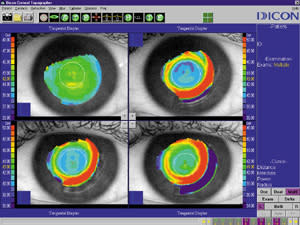

Biomicroscopy usually revealed no corneal signs such as staining or edema. Corneal topography, however, usually showed some degree of central irregularity compared to previous maps (see the six-month [lower right] map in Figure 1). What was the cause of this irregularity, and how could we fix it?

Figure 1. Corneal topography reveals central irregularity after six months of ortho-k lens wear. |